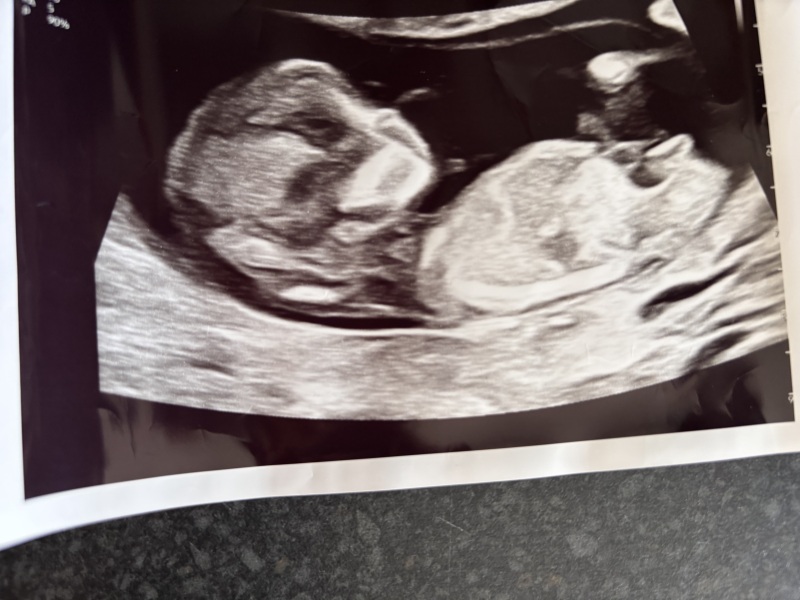

Nub theory…. Can anyone see it? X